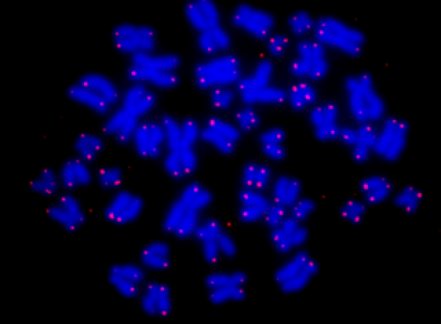

科学家们之所以在太空中开展癌细胞研究,是因为在地球上研究人体细胞行为非常困难,而研究癌细胞复杂的行为方式是攻克癌症的必经之路。人体中的细胞在由蛋白质和碳水化合物组成的支撑结构中生长,地面环境中细胞在重力的作用下会长得扁平而呈片状展开,无法维持正常的三维结构,从而影响细胞的行为方式,为科学家的研究带来难度。这样,长期具有微重力环境的空间站,就成为了研究癌细胞的完美实验室。

在NASA生物反应器内的肿瘤细胞(图片来源:NASA官网)